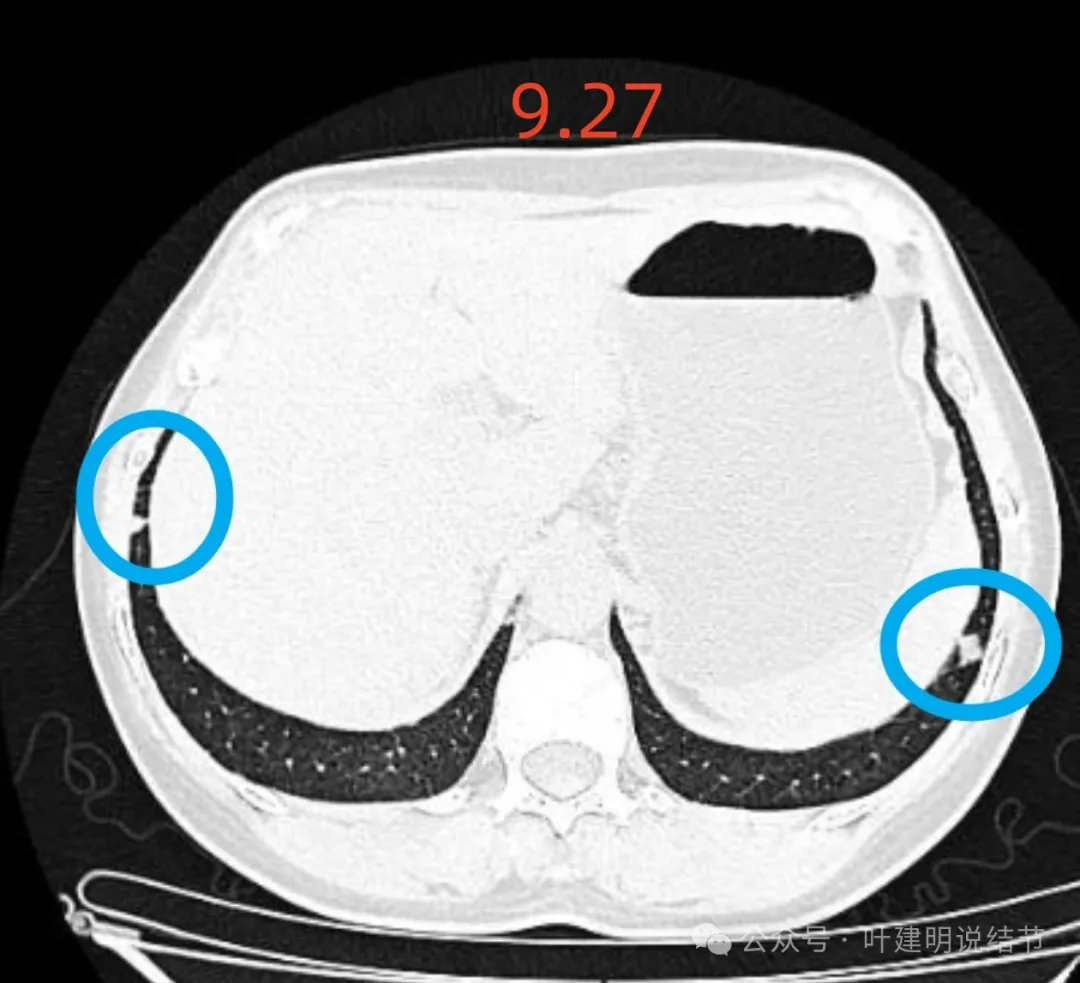

再看2024年9月27号体检时右上后段与左下最明显两处以及实性结节处的影像:

右上与左下混合密度的病灶当时都没有,实性结节是有的。

蓝色的是实性的小结节,缺乏膨胀性,两次检查都有,没有变化,考虑是良性的;红色的这些事10月份检查新增的,这两处比较明显的9月份的时候就是绿色框起来这个区域,当时是没有的。短时间内出现、多发病灶、边缘模糊、轮廓欠清,没有恶性特征,与炎性病变符合。建议查查隐球菌方面的化验,如此结果阳性,请呼吸内科或感染科处理。意见供参考!